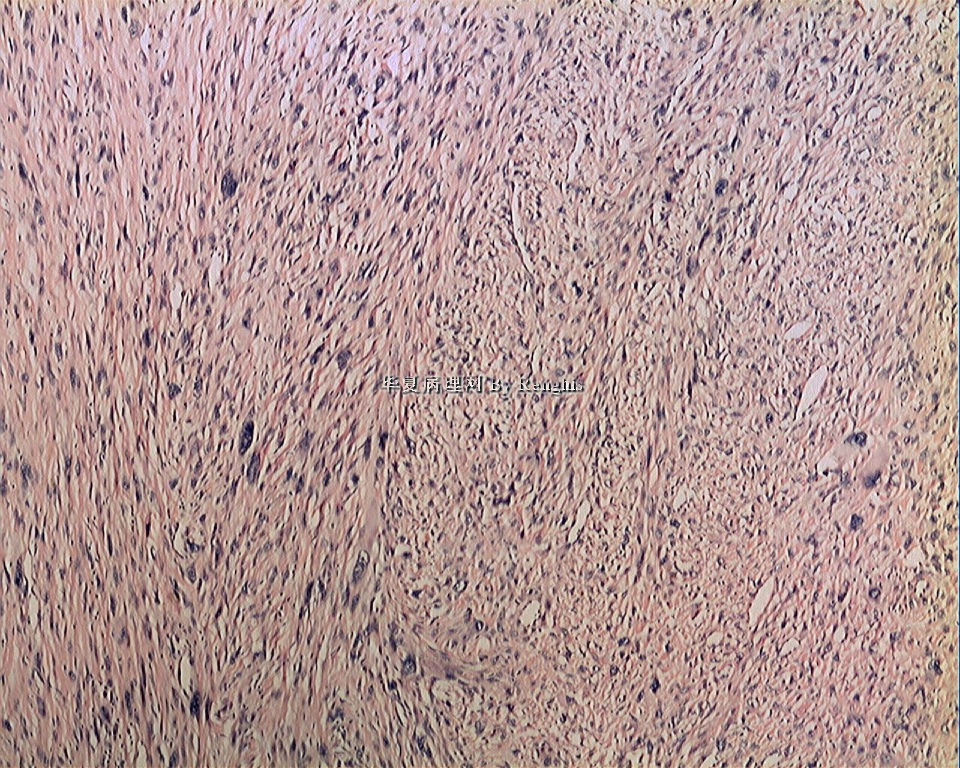

女,29岁,左大腿内侧肿物直径2.8cm,切面灰白、实性、质中,似有包膜。

本例就形态学而言不太符合纤维肉瘤,对于一个多形性和异型明显的肿瘤首先不考虑纤维肉瘤的诊断加上车辐状结构首先还是考虑纤维组织细胞肿瘤。

本人认同此例是一例比较典型的纤维肉瘤,瘤细胞程束状、鱼骨状及编织状排列,部分瘤细胞异型性明显,免疫组化vimentin阳性,SMA灶状弱阳性,desmin阴性,S100阴性,CK阴性,EMA阴性,余记不得了,明天看看再上传。